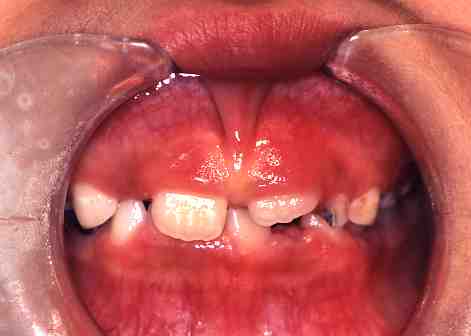

2.術後

この症例は麻酔をして

レーザーにて切除しました。

出血はまったくありませんでした。

3.一週間後